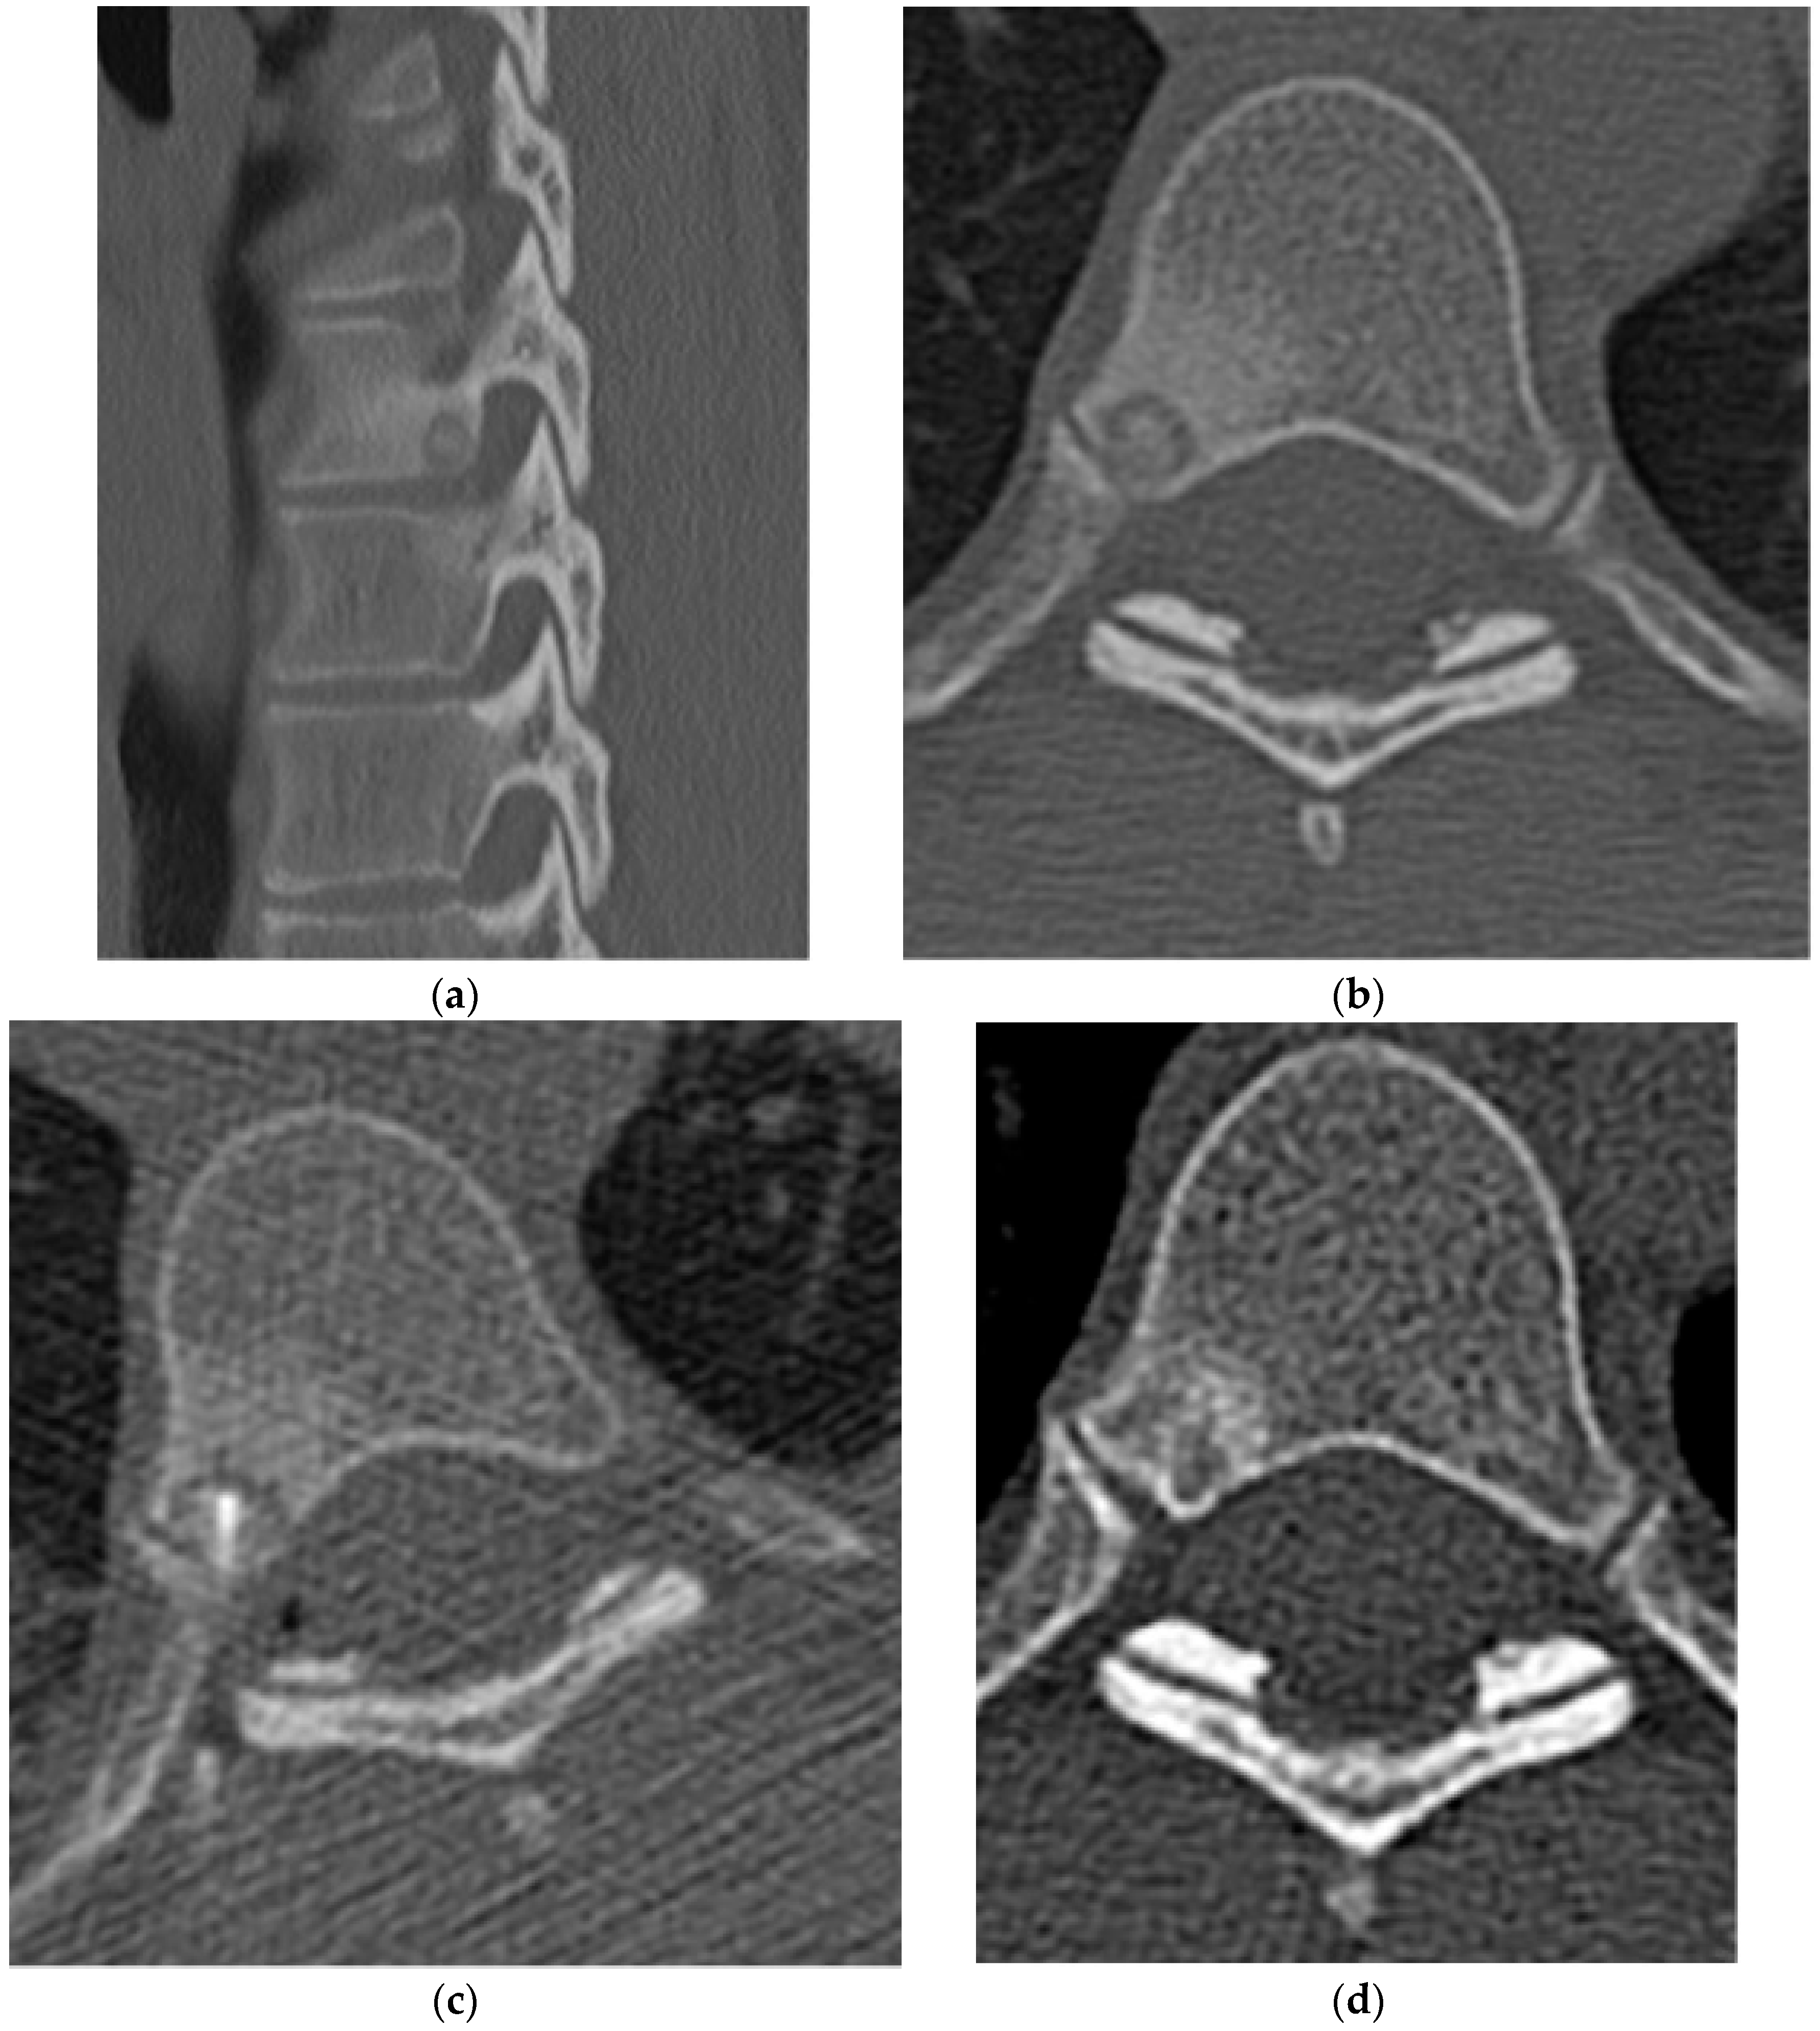

2.2.1. Osteochondroma

2.2.2. Chondroblastoma